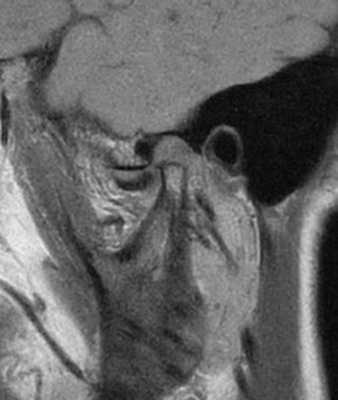

69-летняя пациентка с основными жалобами на боли в проекции челюсти, ограниченное открытие полости рта и невозможностью выдвинуть челюсть вперед обратилась за стоматологической помощью. Со слов пациентки ее симптомы начали развиваться около 6 месяцев назад: именно тогда она заметила, что ей трудно выдвигать челюсть вперед, чтобы посвистеть к своей собаки. По данным анамнеза на протяжении около 50 лет больная отмечала «выскакивание» и «пощелкивание» челюсти с левой стороны, и данные симптомы прекратились приблизительно в то время, когда ей стало трудно выдвигать нижнюю челюсть вперед. В ходе клинического осмотра было обнаружено, что максимальная величина межрезцового расстояния составляла 35 мм, при этом в ходе максимального открытия полости рта челюсть несколько смещалась влево. После массажа и растяжения левой жевательной мышцы и сустава снизилась интенсивность болевых ощущений, однако объем движений не увеличился. Таким образом был поставлен диагноз левостороннего смещения суставного диска без сопровождающейся редукции ВНЧС. Пациентка была направлена на магнитно-резонансную томографию (МРТ), и для исследования локализации и состояния диска при открытом и закрытом рте. Данные МРТ позволили установить, что с левой стороны отмечалось переднее смещение суставного диска в обеих положения, что также подтверждает диагноз смещения без редукции (фото 1-4).

Фото 4. МРТ-скан левого ВНЧС при закрытом состоянии рта: визуализация переднего смещения диска без редукции.